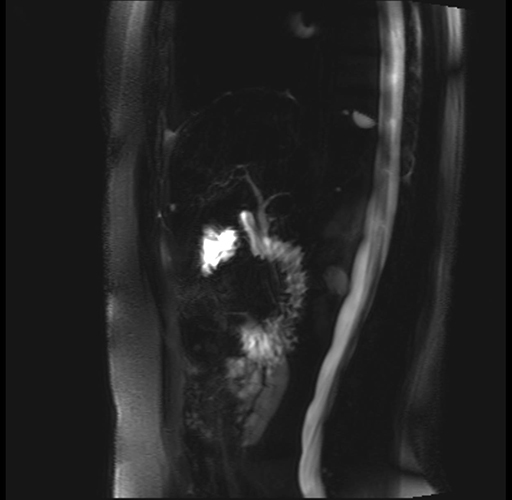

Imaging Analysis

Look through the patient's CT scan to identify any areas of concern for the necessary procedure.

Based on your CT findings, which issue(s) are present and would give reason for "planned slowing down moment(s)" in this case?

Considering a standard distal pancreatectomy procedure, what step(s) of the operation would you do differently in this case?